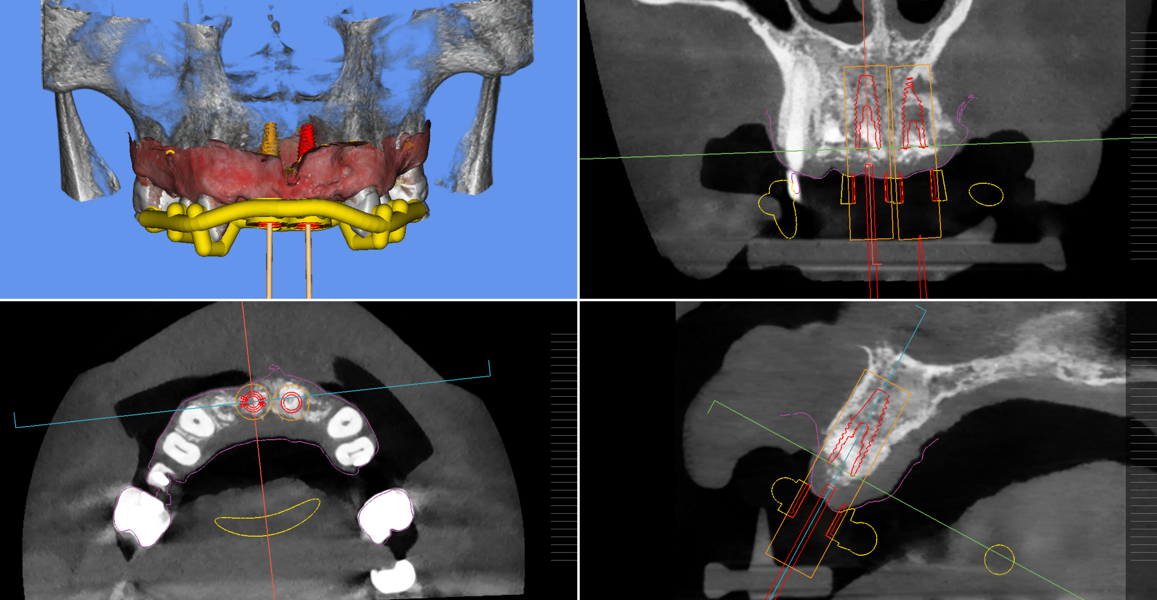

During the implant planning phase, we created a preliminary plan using 3D imaging software with a prosthetically driven implant planning approach (Figs. 9 & 10), and the plan was exported into surgical guide planning software for final planning and construction of the surgical drilling guide (Figs. 11a–c). The implants were planned in all four positions with the object of identifying the two most optimal and accessible sites for the placement of two implants and the corresponding bridge restoration.

Figs. 11a–c: Implant planning and guided surgical guide design.

Fig. 11b.

Fig. 11c.